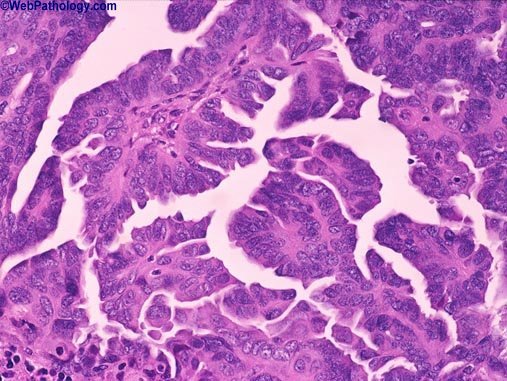

List three risk factors for developing this lesion.

Cystitis glandularis

Urachal remnant

Exstrophy

(Adenocarcinoma - look for pleiomorphic cells lining glands)